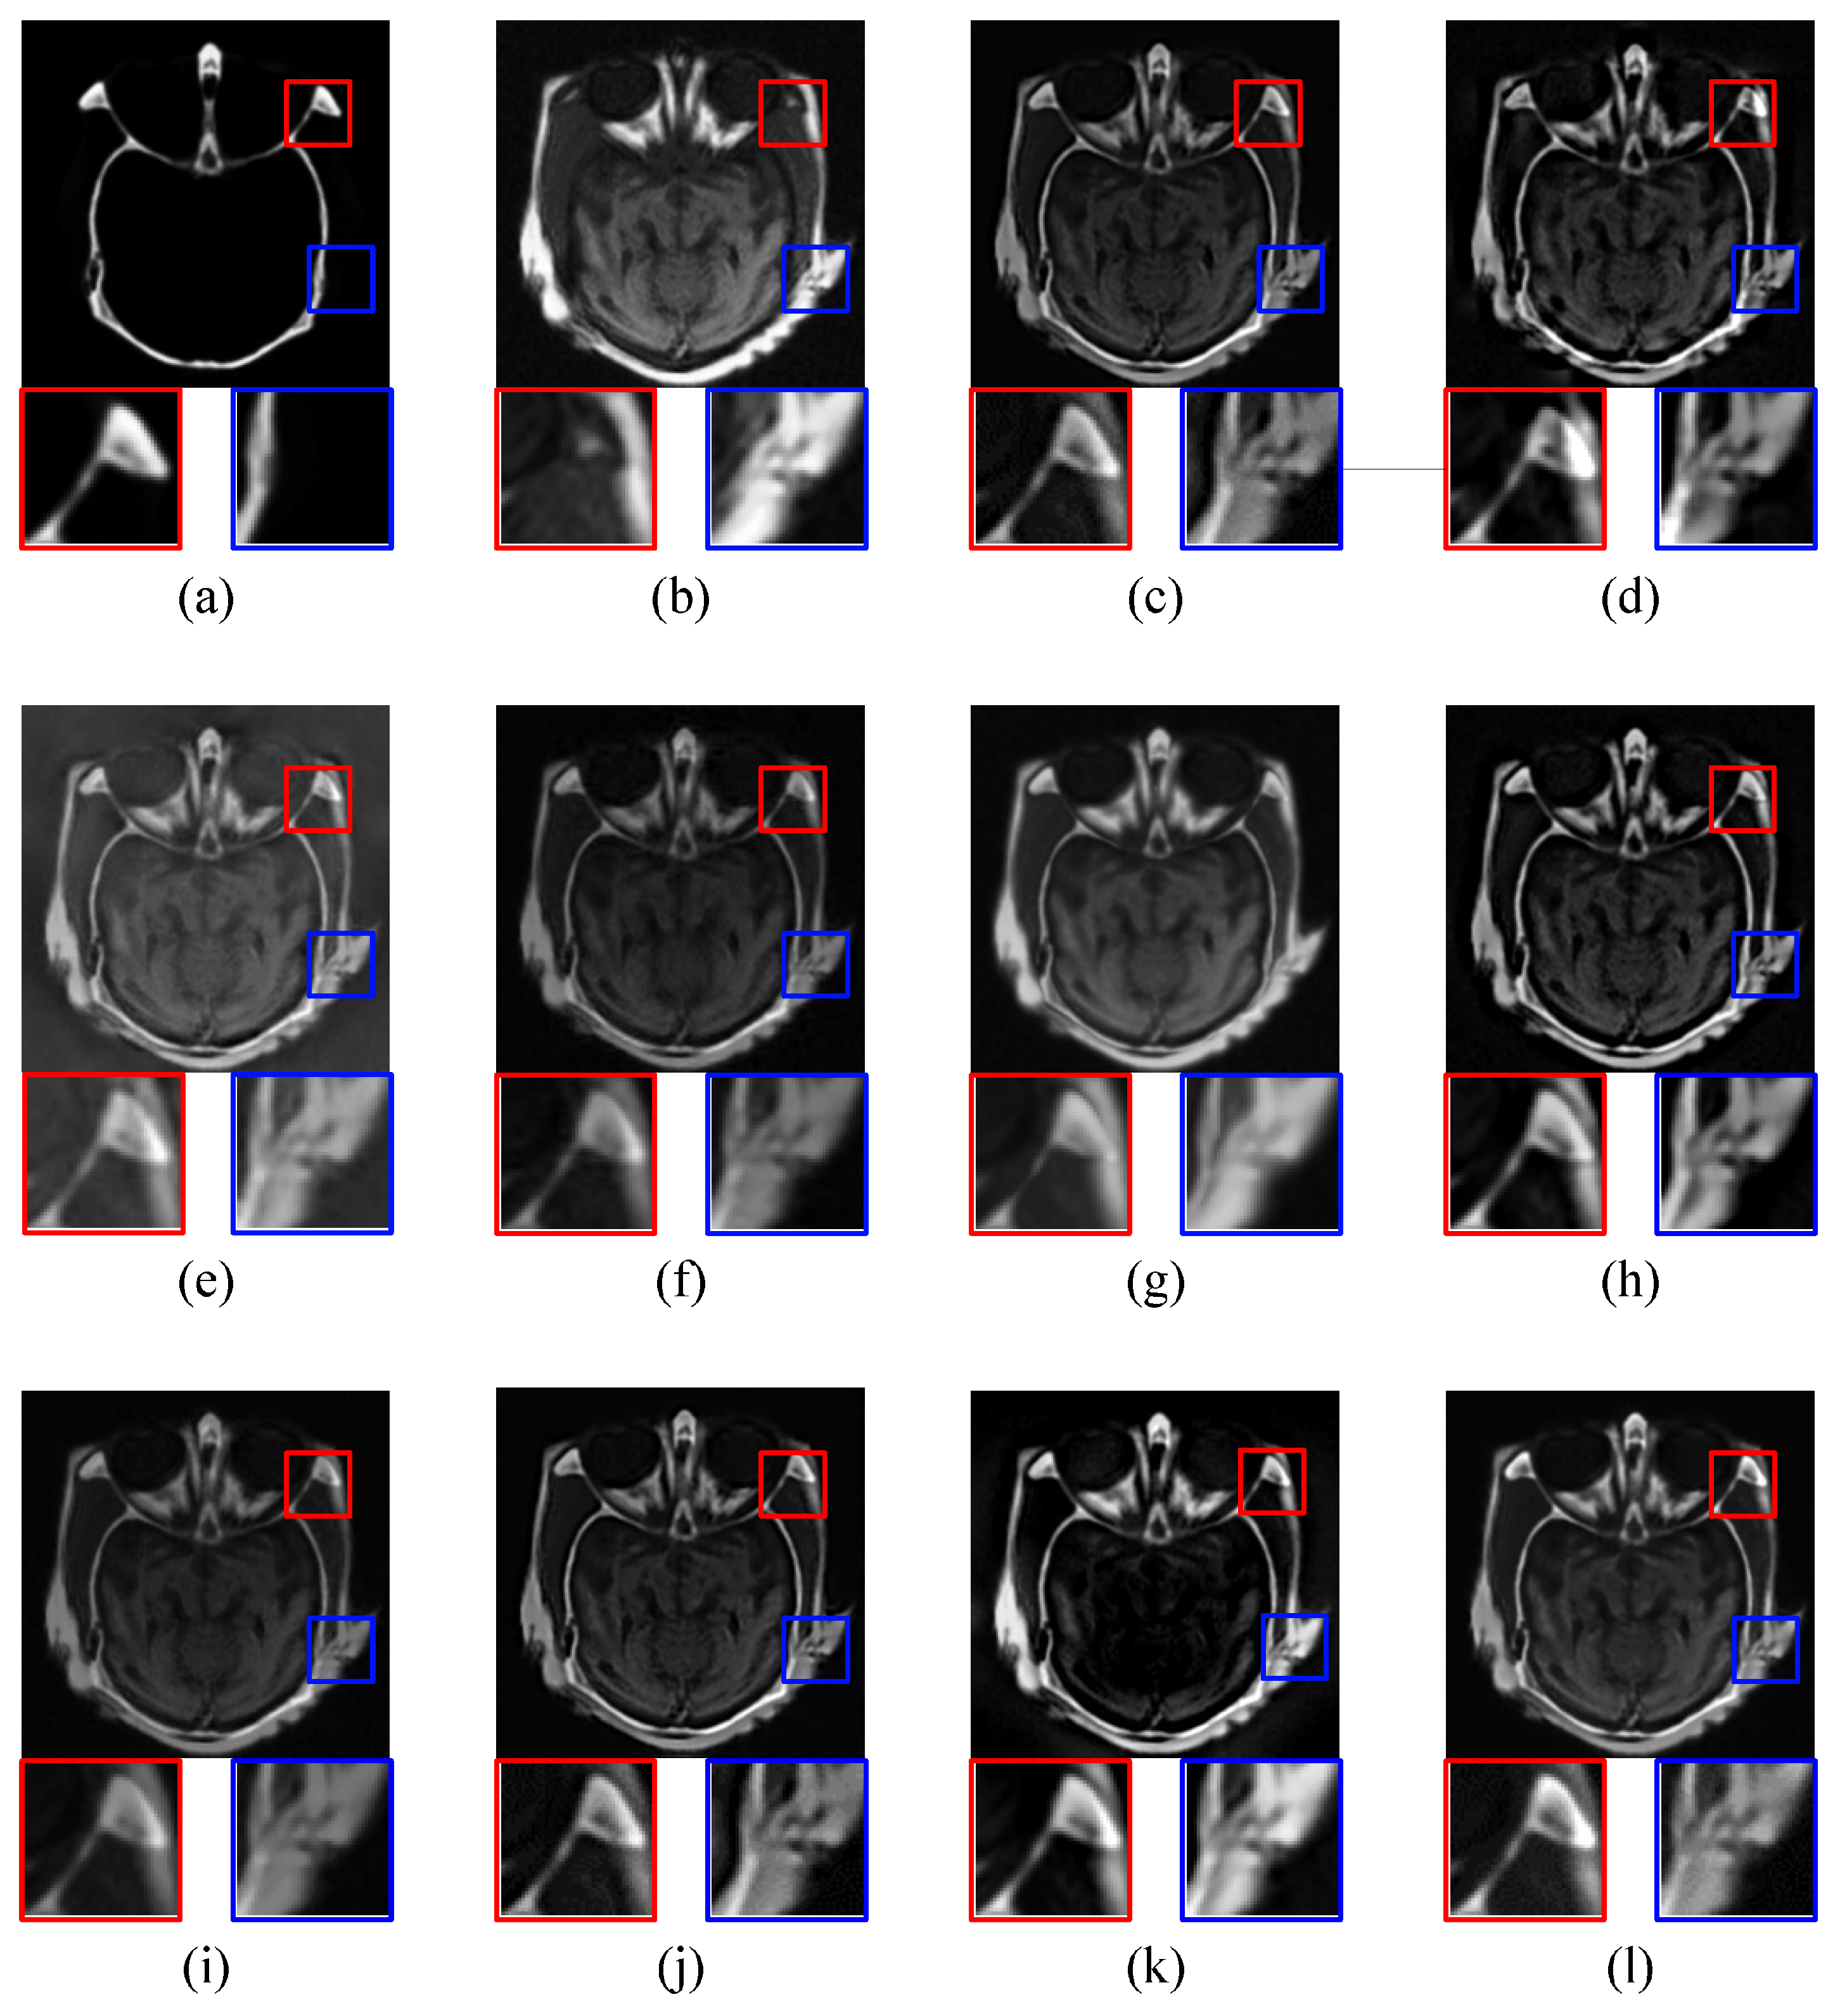

4.2.1. CT-MRI Image Fusion Comparative Experiments